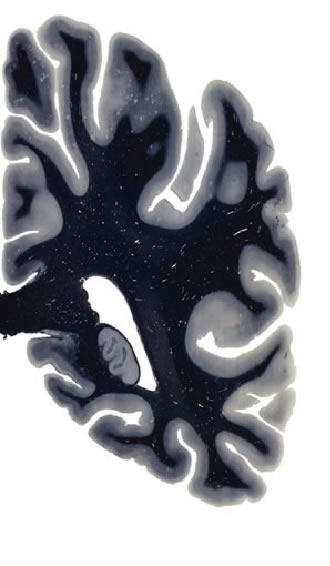

Hi-Resolution Sections · Cells (Nissl Staining) · Virtual Microscopy

Frontal sections (Nissl) from the Atlas Brain:

Slice ID:

r4-0320

Plate NR:

53

Position:

45,4 mm